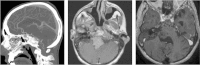

Introduction Malignancies of the clivus and petroclival region are mainly chordomas and chondrosarcomas. Although a spectrum of malignancies may present in this area, a finite group of commonly encountered malignant pathologies will be the focus of this review, as they are recognized to be formidable pathologies due to adjacent critical neurovascular structures and challenging surgical approaches. Objectives The objective is to review the literature regarding medical and surgical management of malignant tumors of the clival and petroclival region with a focus on clinical presentation, diagnostic identification, and associated adjuvant therapies. We will also discuss our current treatment paradigm using endoscopic, open, and combined approaches to the skull base. Data Synthesis A literature review was conducted, searching for basic science and clinical evidence from PubMed, Medline, and the Cochrane Database. The selection criteria encompassed original articles including data from both basic science and clinical literature, case series, case reports, and review articles on the etiology, diagnosis, treatment, and management of skull base malignancies in the clival and petroclival region. Conclusions The management of petroclival malignancies requires a multidisciplinary team to deliver the most complete surgical resection, with minimal morbidity, followed by appropriate adjuvant therapy. We advocate the combination of endoscopic and open approaches (traditional or minimally invasive) as required by the particular tumor followed by radiation therapy to optimize oncologic outcomes.